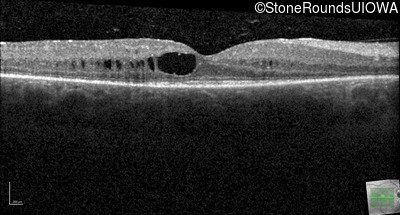

Optical Coherence Tomography - Right - 20/30 -2

Exemplar / OCT Stack